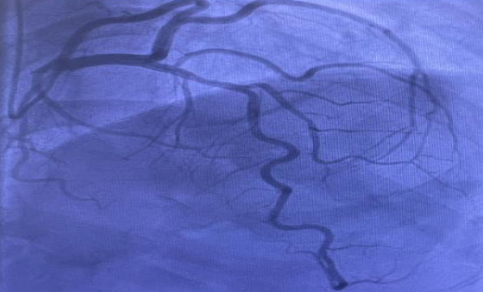

Coronary angiography (Figure 6) confirmed minor disease in one artery but no significant coronary artery disease. Despite this, the cardiac MRI findings were most suggestive of an ischemic aetiology (left circumflex territory myocardial infarction) rather than sarcoidosis.

Figure 6:Coronary angiogram showed focal minor disease in the mid left anterior descending artery (10% stenosis), but was otherwise entirely normal i.e., there was no significant coronary artery disease.